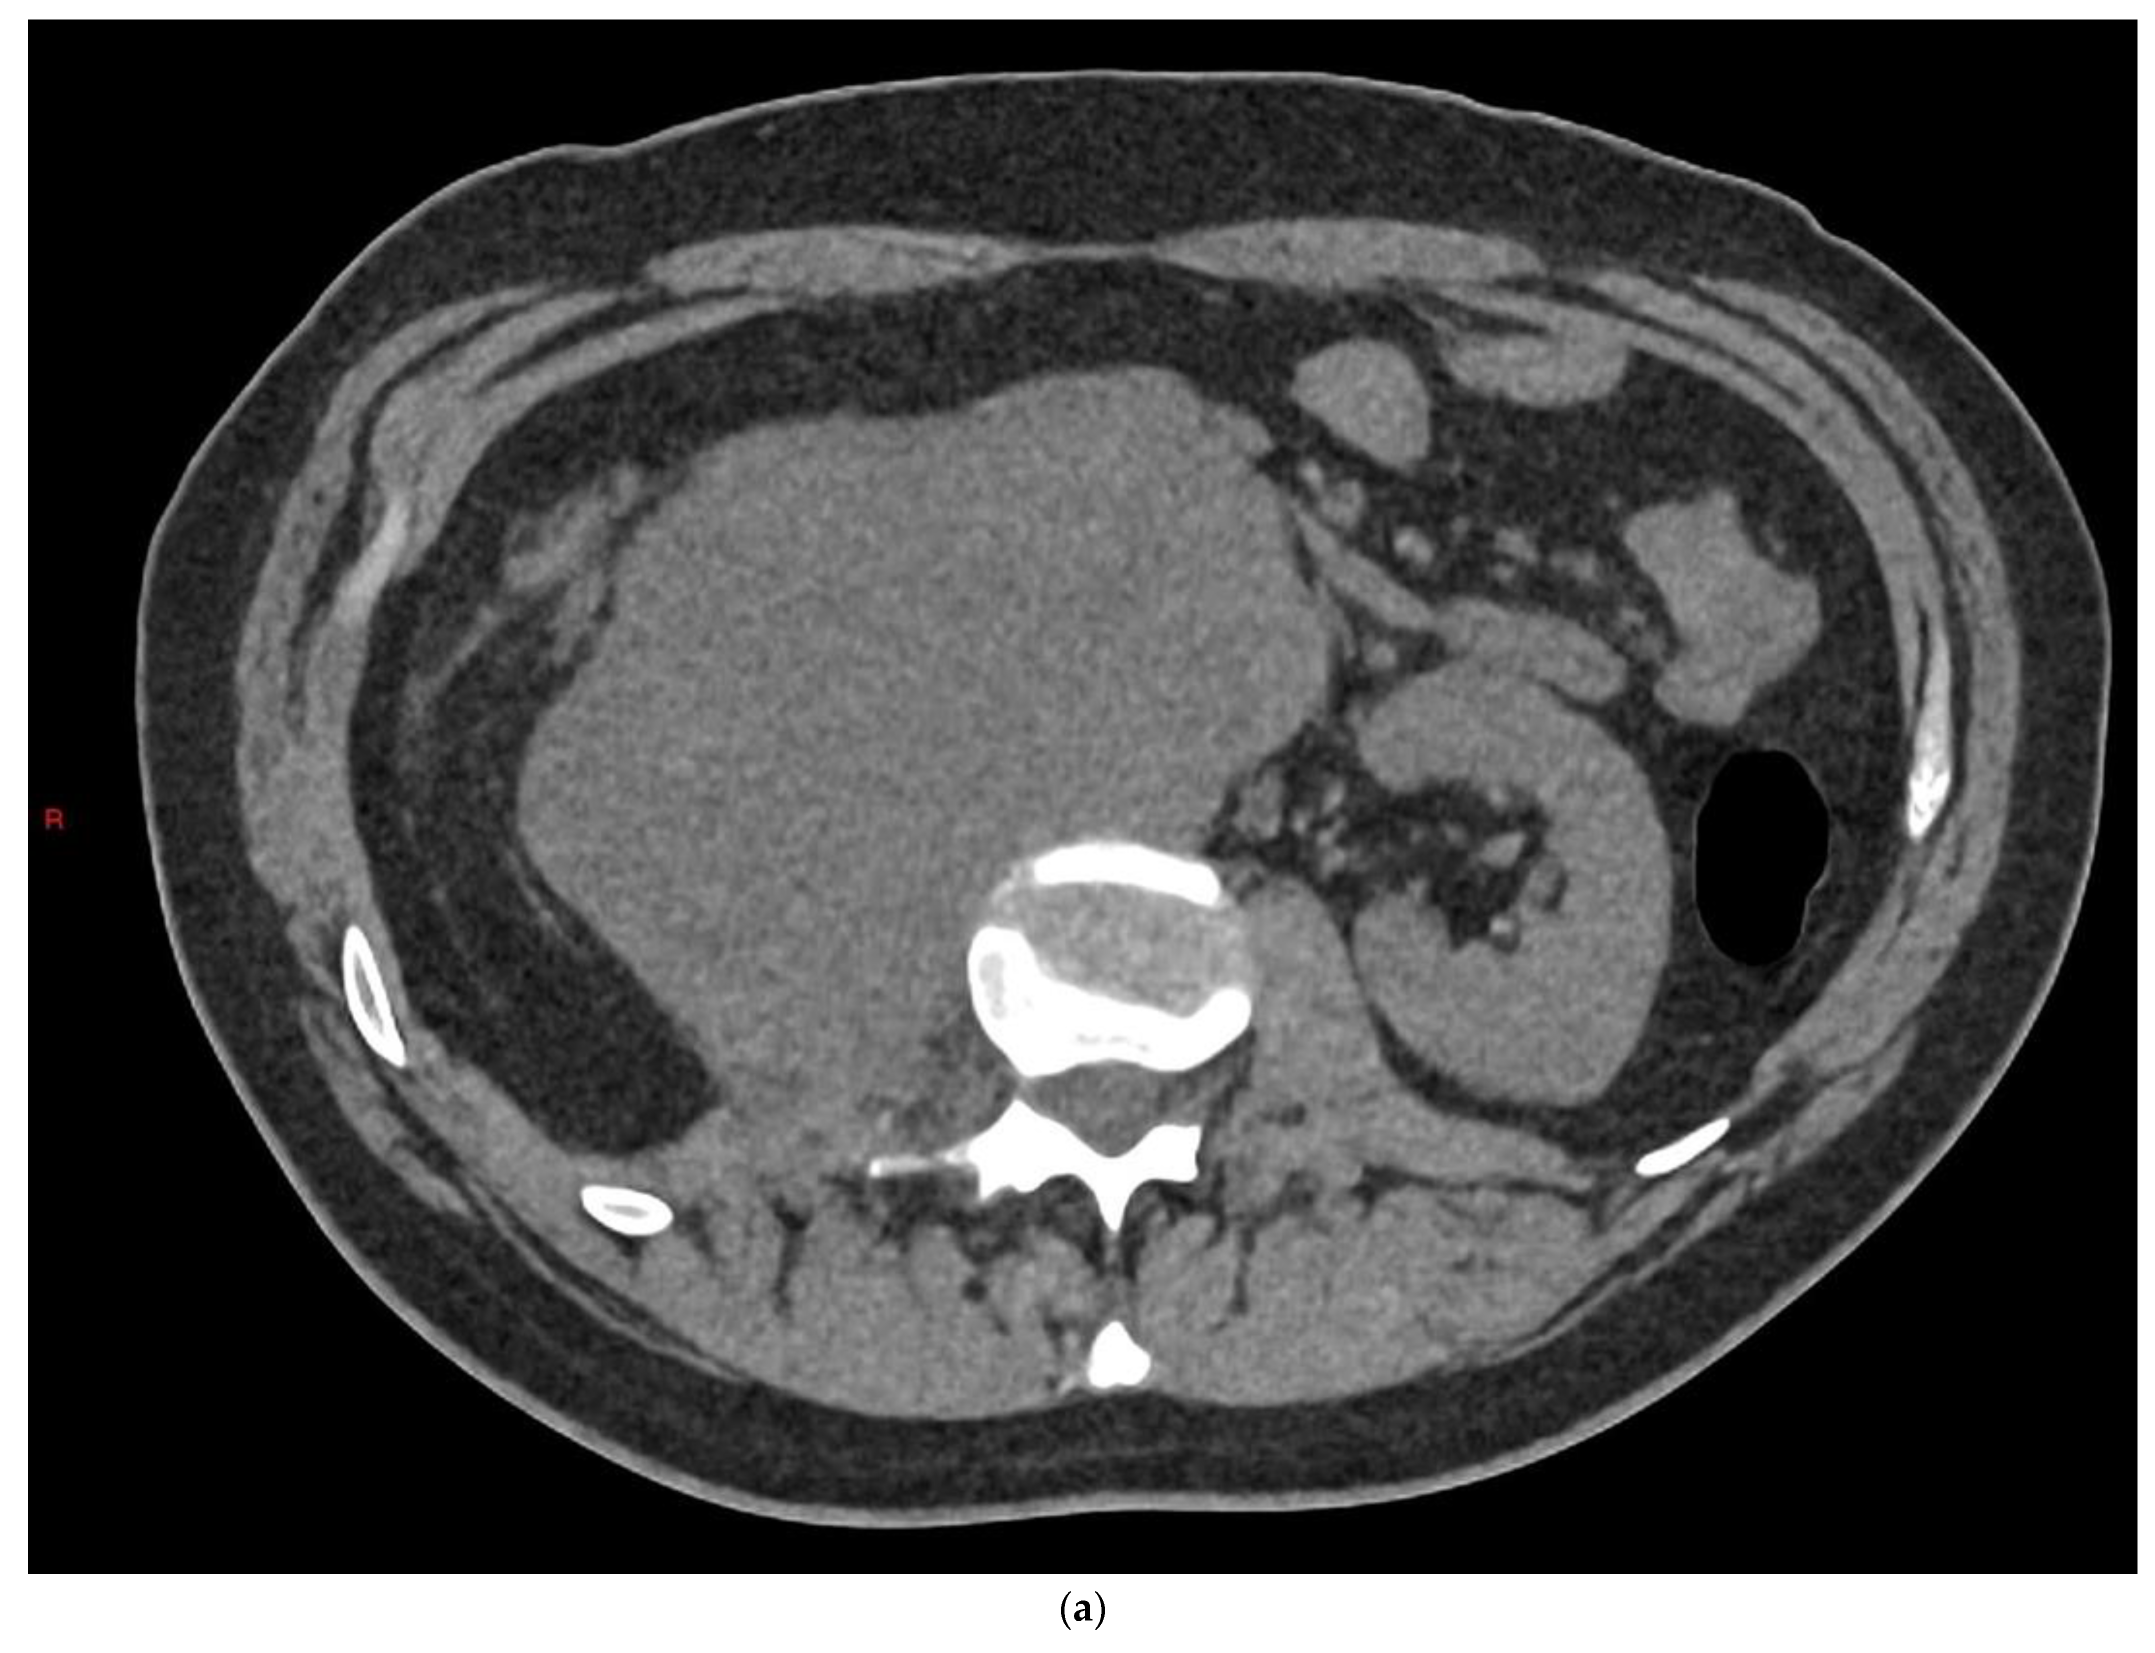

4.1. Seminomatous Germ Cell Tumour

4.2. Non-Seminomatous Germ Cell Tumour (NSGCTs)